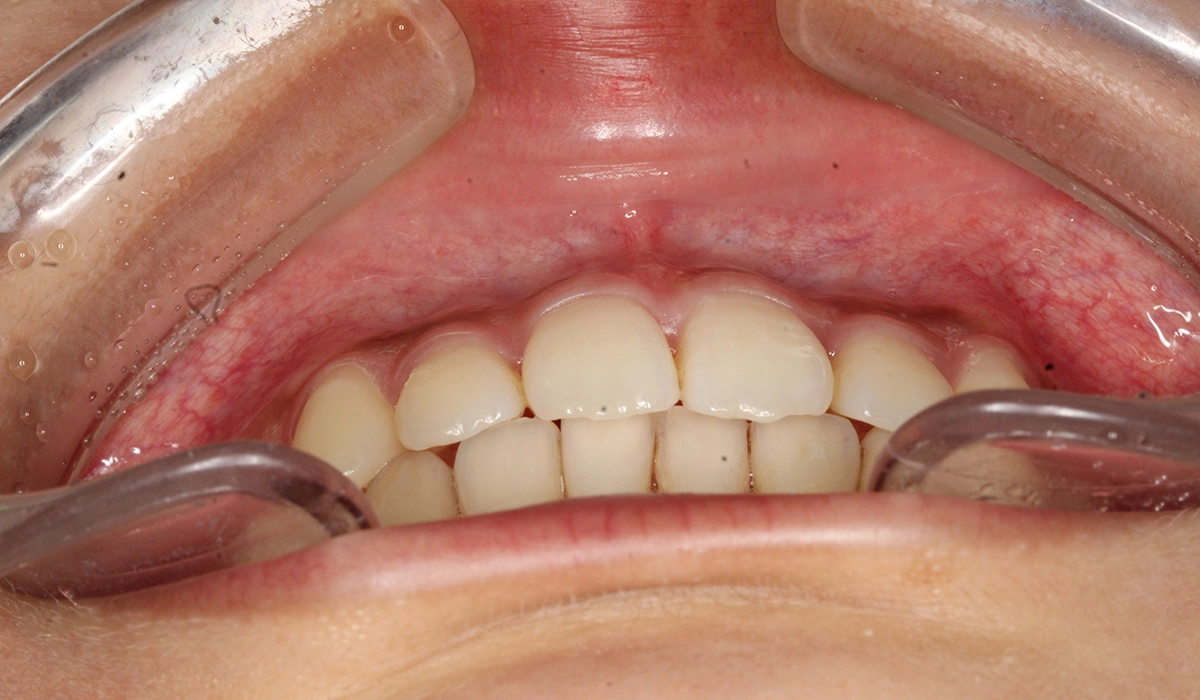

今回ご紹介する患者様は、左上の歯並びを気にされており、矯正検査後叢生Ⅰ級と診断しました。

術前:正面

| 主訴 | 左上の歯並びが気になる |

| 治療期間 | 14カ月 |

| 治療費用 | 880,000円(税込) |

| 治療内容 | 左上の歯並びを気にされており、矯正検査後叢生Ⅰ級と診断しました。 |